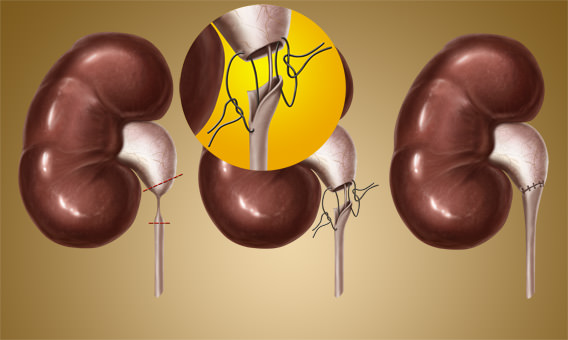

Интраренальная лоханка: рентгеновские снимки и примеры